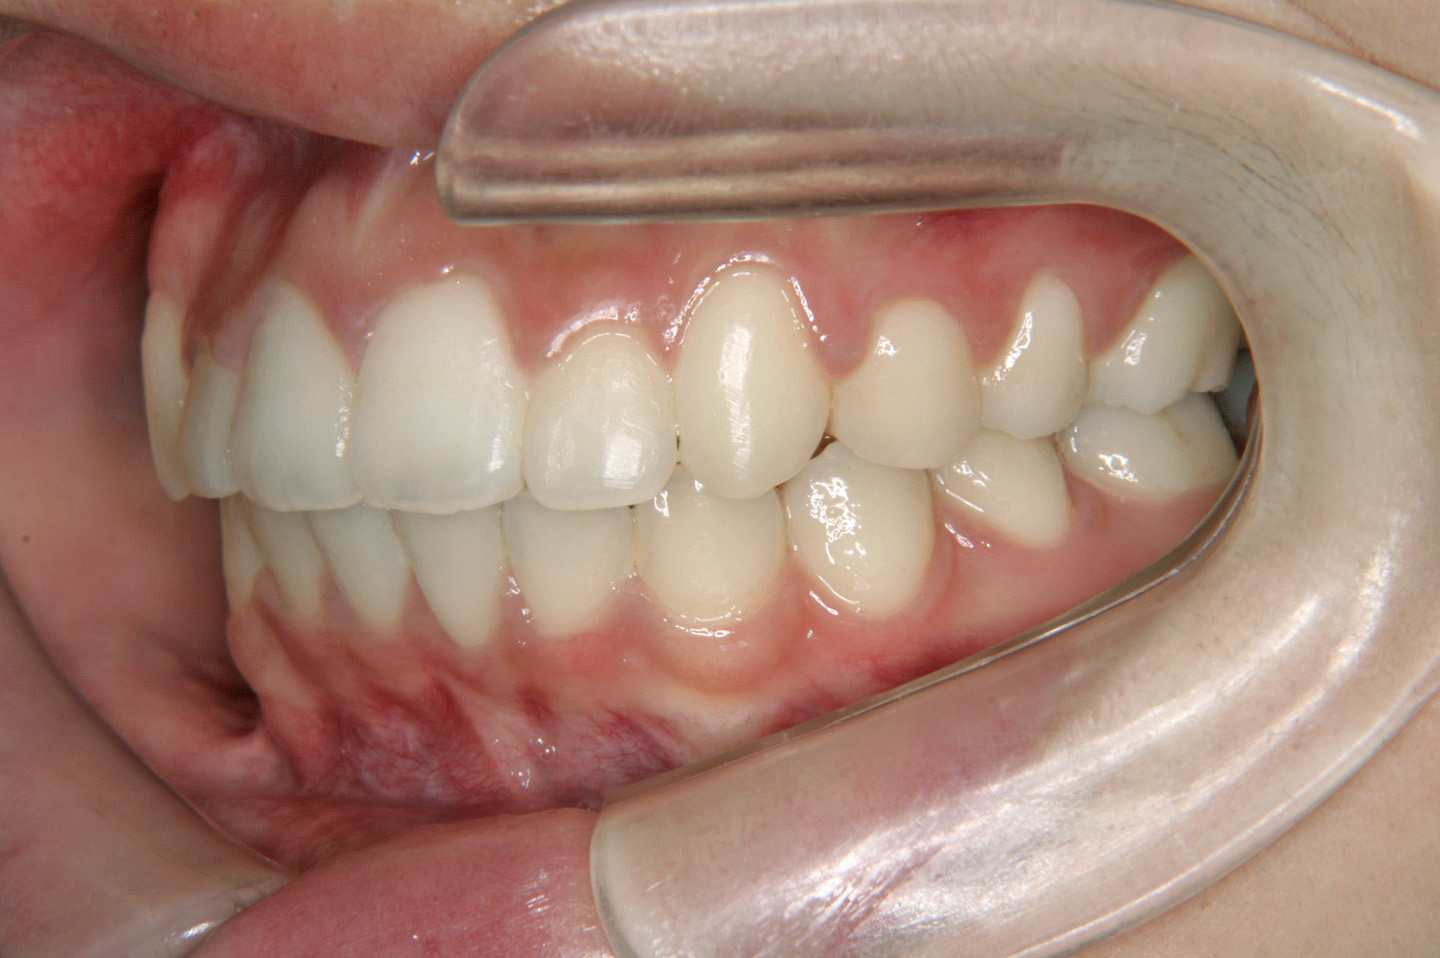

八重歯を気にされて来院された10歳の女子です。上顎の叢生の程度は中程度で上顎第二大臼歯の萌出前であったので、ヘッドギアーとセクショナルアーチを用い、大臼歯の後方への拡大を行いました。その後、その空隙を利用して、非抜歯でエッジワイズ装置を用いて配列を行いました。拡大治療に2年、後期3年で治療いたしております。